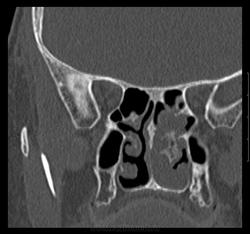

Женщина 1954г.р. обратилась к доктору 20.06.13г. с жалобами на головные боли, головокружение, тошноту. DS: энцефалопатия сложного генеза, ГБ, ШОХ. Отправлена МРТ г.м от 19.07.13г.- общая сообщающаяся гидроцефалия заместительного характера, TR клетках решетчатой кости, рекомендовано КТ. На приеме у ЛОР 26.0713г.: жалобы на затруднение носового духания; объективно- полипозная ткань в нос.пазухах слева. После проведенного КТ 30.07.13г. позвонил пациентке, говорит что примерно раз в три месяца бывают носовые кровотечения даже в горизонтальном положении. Что думаете коллеги?

Вот ее снимки.

Дополнительное образование в носовых раковинах слева ( или справа? у нас в МРТ это левая сторона ) с признаками обызвествления.Носовые раковины разрушены.Думаю, что точно нужно оперировать.

Левая сторона. Дело не в том, что нужна или нет операция. По моему это добро, но какое??? Хондромиксоидная фиброма? хондрома? Прилежащие костные и хрящевые структуры без признаков деструкции. У образования костно- хрящевая основа. Или я не в ту степь думаю...)